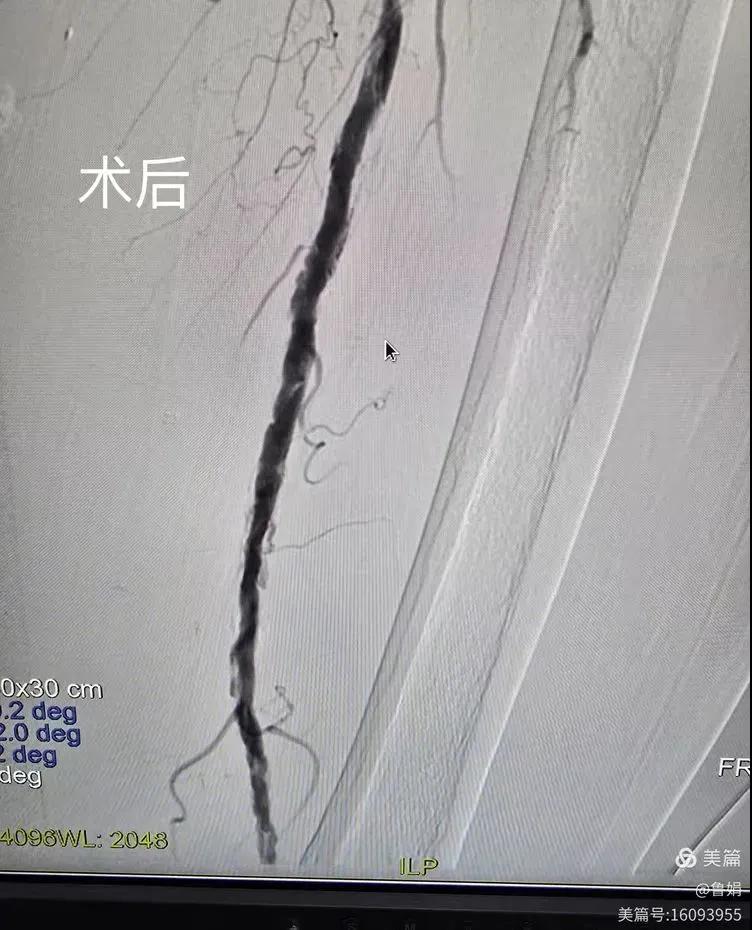

據(jù)悉,該患者,女,73歲,下肢動脈硬化閉塞癥,“以靜息痛,間歇性跛行”入院,CTA評估:股淺動脈,腘動脈間斷性多段重度狹窄,外二科血管外科團隊根據(jù)患者病情,結(jié)合檢查結(jié)果,經(jīng)過科室會診后,決定對該病人行介入治療。手術(shù)由周創(chuàng)業(yè)副主任與北大一院血管外科專家郭宏杰教授聯(lián)合開展,對股淺動脈,腘動脈重度閉塞段行血管開通+藥涂球囊擴張成形,術(shù)后狹窄明顯緩解,血流恢復(fù)!

下肢動脈閉塞的介入開通是外周介入領(lǐng)域難度最大的技術(shù)之一,這項微創(chuàng)介入手術(shù)的開展,實現(xiàn)了漯河市中醫(yī)院在下肢動脈血管介入治療上零的突破,進一步推動了醫(yī)院介入治療技術(shù)的發(fā)展,讓患者足不出戶就能切實享受到優(yōu)質(zhì)的醫(yī)療資源,極大方便了患者就醫(yī)。(介入中心:魯娟)